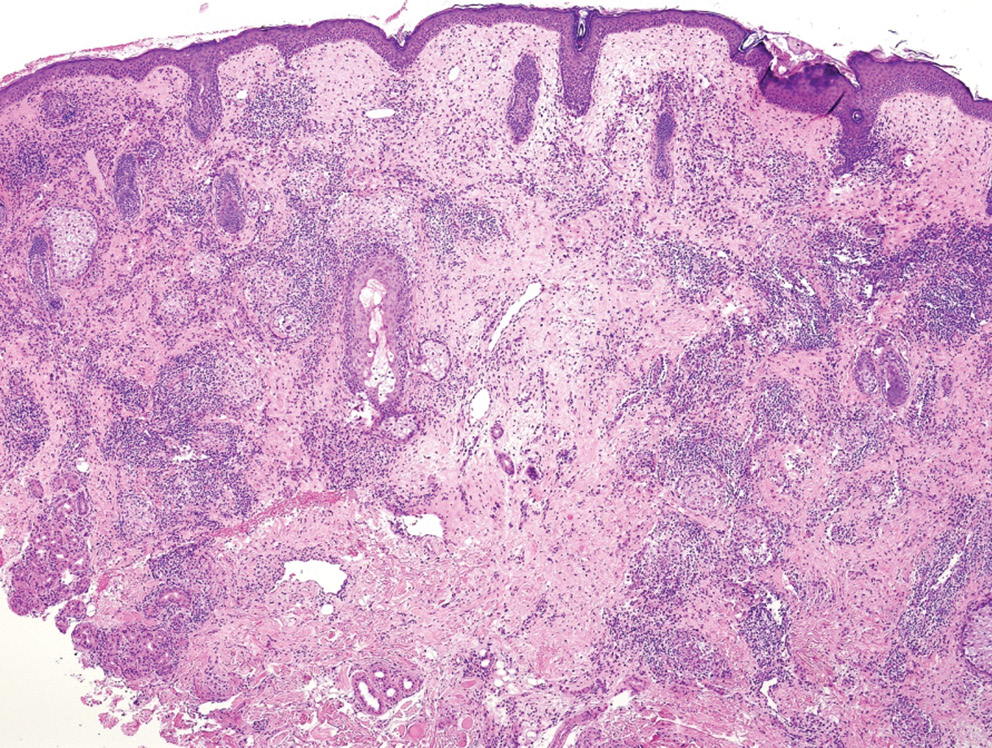

С целью уточнения диагноза проведена диагностическая биопсия кожи. При гистологическом исследовании в дерме на фоне отека были обнаружены многочисленные мелкие эпителиоидно-клеточные гранулемы саркоидного типа, без признаков казеозного некроза. К некоторым гранулемам прилегали очаговые лимфоцитарные инфильтраты (рис. 2, 3). При окраске PAS и по Циль–Нильсену микрорганизмов не выявлено.

Рис. 2. Гранулематозный инфильтрат в дерме на фоне отека

Fig.2. Granulomatous infiltrate in the dermis with edema

Рис. 3. Дермальные инфильтраты из многочисленных мелких гранулем саркоидного типа без признаков казеозного некроза. К некоторым гранулемам прилегают очаговые лимфоцитарные инфильтраты

Fig. 3. Dermal infiltrates consisting of numerous small sarcoid-type granulomas without signs of caseous necrosis. Some granulomas are adjacent to focal lymphocytic infiltrates